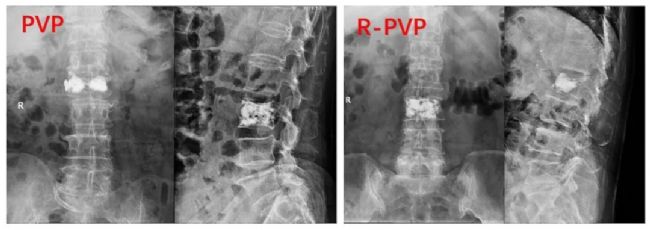

術(shù)后X線顯示骨水泥的彌散。與PVP組相比,R-PVP組在術(shù)后X線片上表現(xiàn)出更強的在椎體中線的融合能力。